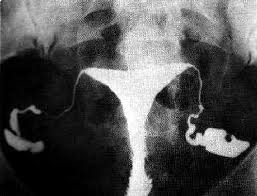

Yapılan bir çok araştırma göstermiştir ki HSG yani ilaçlı rahim filmi çekilmesi sonrasında ilk 6 ayda gebelik oranı hiç HSG çekilmeyen hastalara göre fazladır. Burada bahsedilen oran artışı kısırlık ile ilgili bir ilaç tedavisi verilmemesine rağmen kendiliğinden oluşan gebeliklerle gözlenmiştir. Yani rahim filmi sadece tanısal amaçlı bir işlem değildir, bu şekilde infertil hastaların aynı zamanda tedavisine de yardım eden bir işlemdir. (tubal flushing) HSG sonrası gebelik oranında artış olmasının sebebi rahim ve tüplerin içerisine basınçla verilen sıvının tüplerdeki küçük tıkaçları açması, tüpleri gererek ufak yapışıklıkları açması, tüplerde antibakteriyel etki oluştırması olabilir.

Rahim filmi çekilirken rahim içerisine ince bir kateter yardımıyla ilaç verilir. Bu ilaç sıvı bir kontrast maddedir, yani röntgen filminde görülebilecek bir sıvıdır. Bu sıvı yağ bazlı veya sıvı bazlı üretilebilmektedir. Yukarıda bahsedilen gebelik şansını arttırıcı etkinin yağ bazlı sıvılarla çekilen HSG sonrasında daha fazla arttığı gösterilmiştir bazı çalışmalarda.